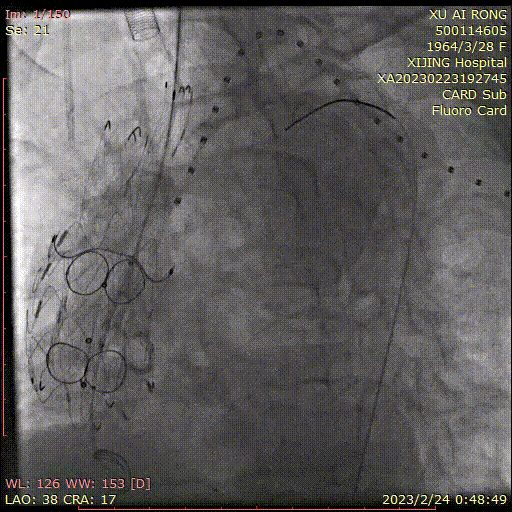

★ 病例4

王某,女,56岁,“突发胸背痛15小时”入院,主动脉CTA提示:升主动脉-腹主动脉管腔外可见新月形低密度影,主动脉弓前部可见溃疡,大小约0.6cm。

术前CTA

术前造影

术后造影

手术用时 95分钟